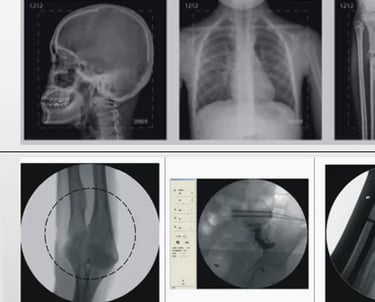

Mobile Surgical Dynamic C-Arm X-Ray Machine

The Mobile Surgical Dynamic C-Arm X-Ray Machine is a versatile and compact medical imaging device used for real-time fluoroscopic imaging during surgical and diagnostic procedures. It features a "C-arm" design, allowing for flexible positioning and maneuverability around patients during various types of surgeries, especially orthopedic and vascular procedures. This mobile system is equipped with advanced imaging technology, providing high-quality images while minimizing radiation exposure. Its compact and mobile nature makes it an essential tool in the operating room, emergency departments, and other clinical settings.

Fluoroscopy and Radiography: Offers both real-time fluoroscopic imaging and high-quality still images for detailed analysis, giving surgeons flexibility during procedures.

3D Imaging (Optional in some models): Some mobile C-arms can generate 3D images from fluoroscopic data, useful for complex orthopedic surgeries or imaging of soft tissues.

Orthopedic Surgeries:

Ideal for real-time imaging during bone, joint, and spine surgeries. It helps guide the surgeon during procedures like fracture reduction, pinning, or implant placement.

Cardiovascular Procedures:

Employed during interventional cardiology or vascular surgeries to visualize blood vessels, heart conditions, and stent placements in real-time.